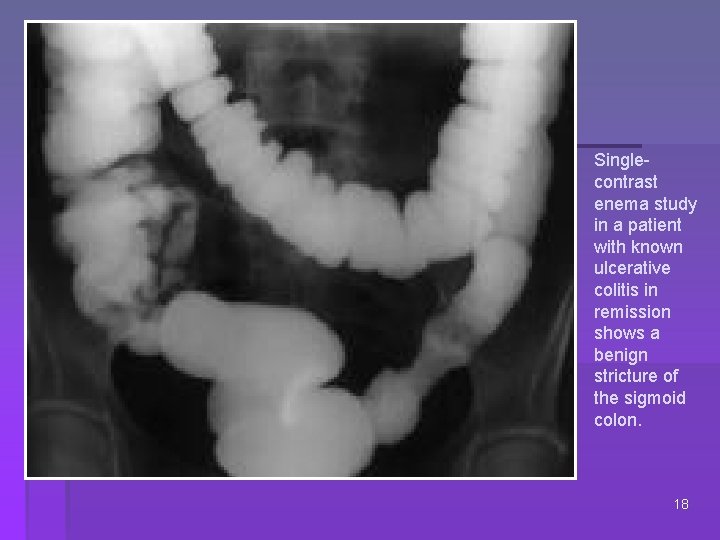

Singlecontrast enema study in a patient with known ulcerative colitis in remission shows a benign stricture of the sigmoid colon. 18